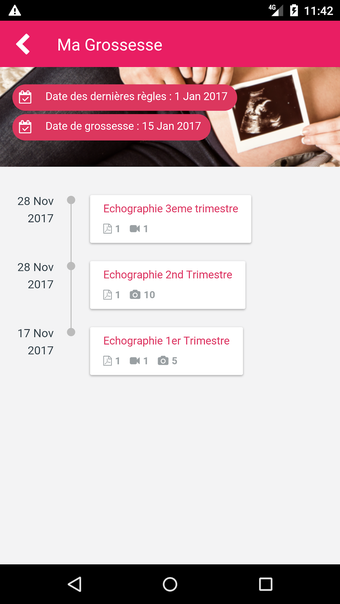

A free app for Android, by MonEcho.

MediFile is an application for medical professionals to manage all of their ultrasound images, reports, and other patient data in one place. The application allows them to scan, view, and save their files directly from their device. The application has the capability to upload reports to the server of the doctor or midwife, for whom the report was sent.

The main advantage of the application is that it makes it very easy for the medical professional to view and share their patient's data with their colleagues. It also facilitates the creation of a patient database and a communication channel for all of the medical professionals working on the same case.